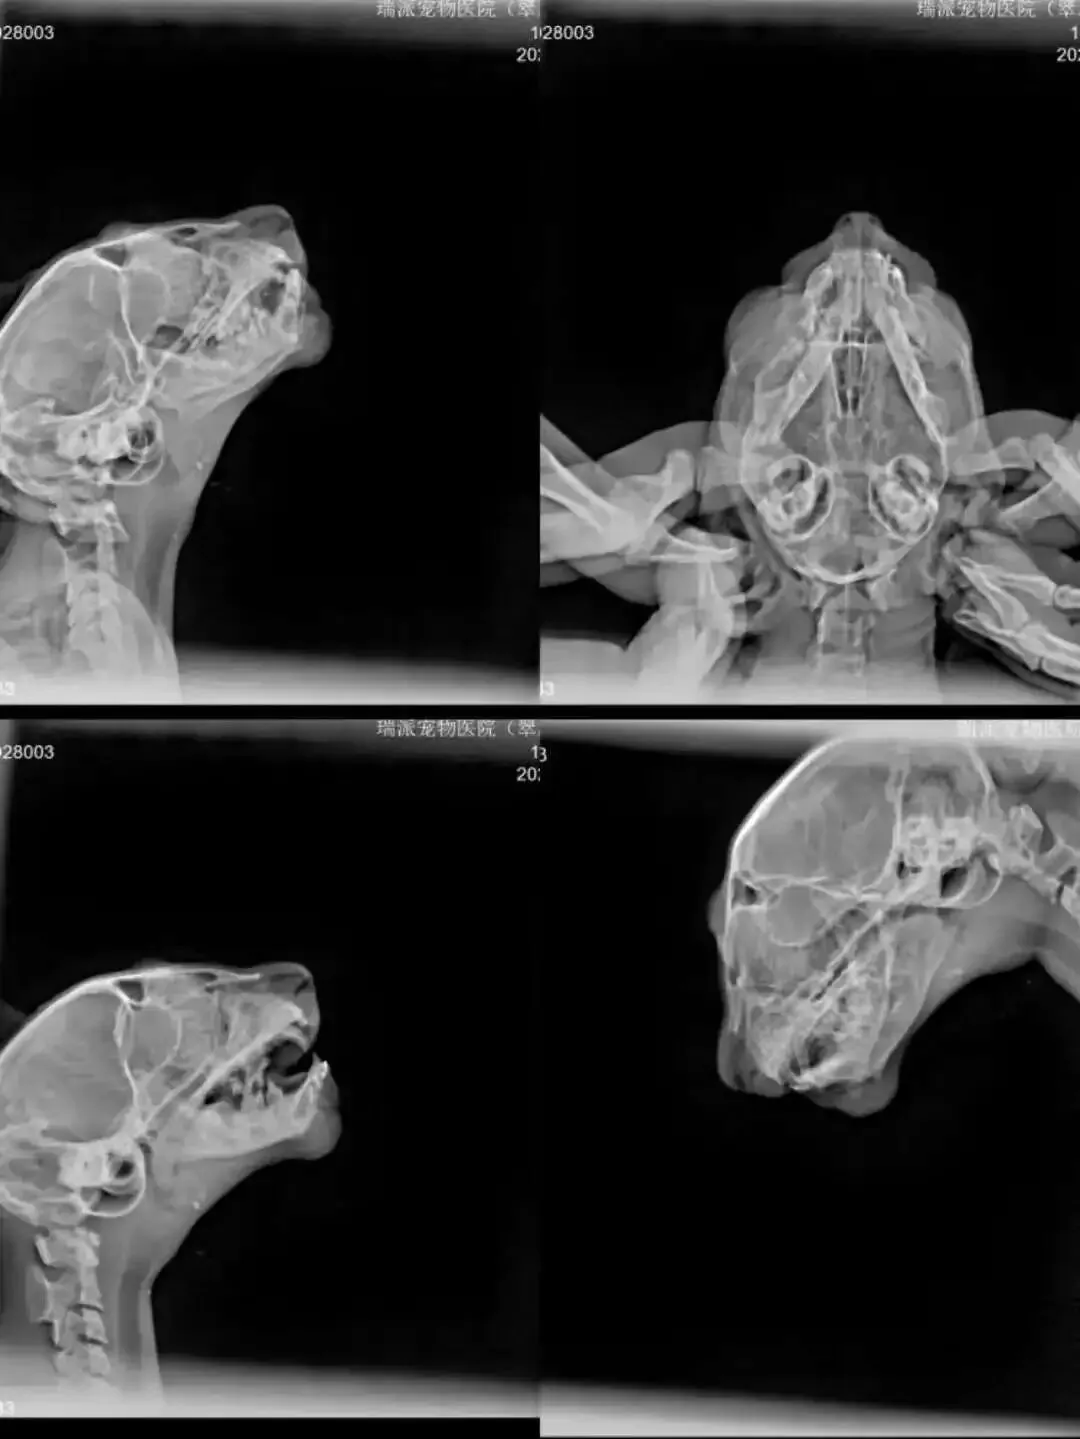

如墨救助进展

阴阳脸小猫“如墨”于9月26日现身校园,在草丛中不停叫唤,群友留意到其下巴鲜红、进食姿态有异,遂果断抓捕送医。经过检查发现如墨体重仅0.8kg,下巴皮肉分离并伴有骨折,因其年龄与体重过小,先行住院护理观察。令人欣慰的是,如墨展现出顽强的生命力,努力干饭、积极配合,恢复情况超出预期——下巴皮肉逐渐愈合,且无需骨科手术。目前它在寄养家庭中继续康复,亲人亲猫,现正为它寻找一个能永远遮风避雨、不离不弃的家。